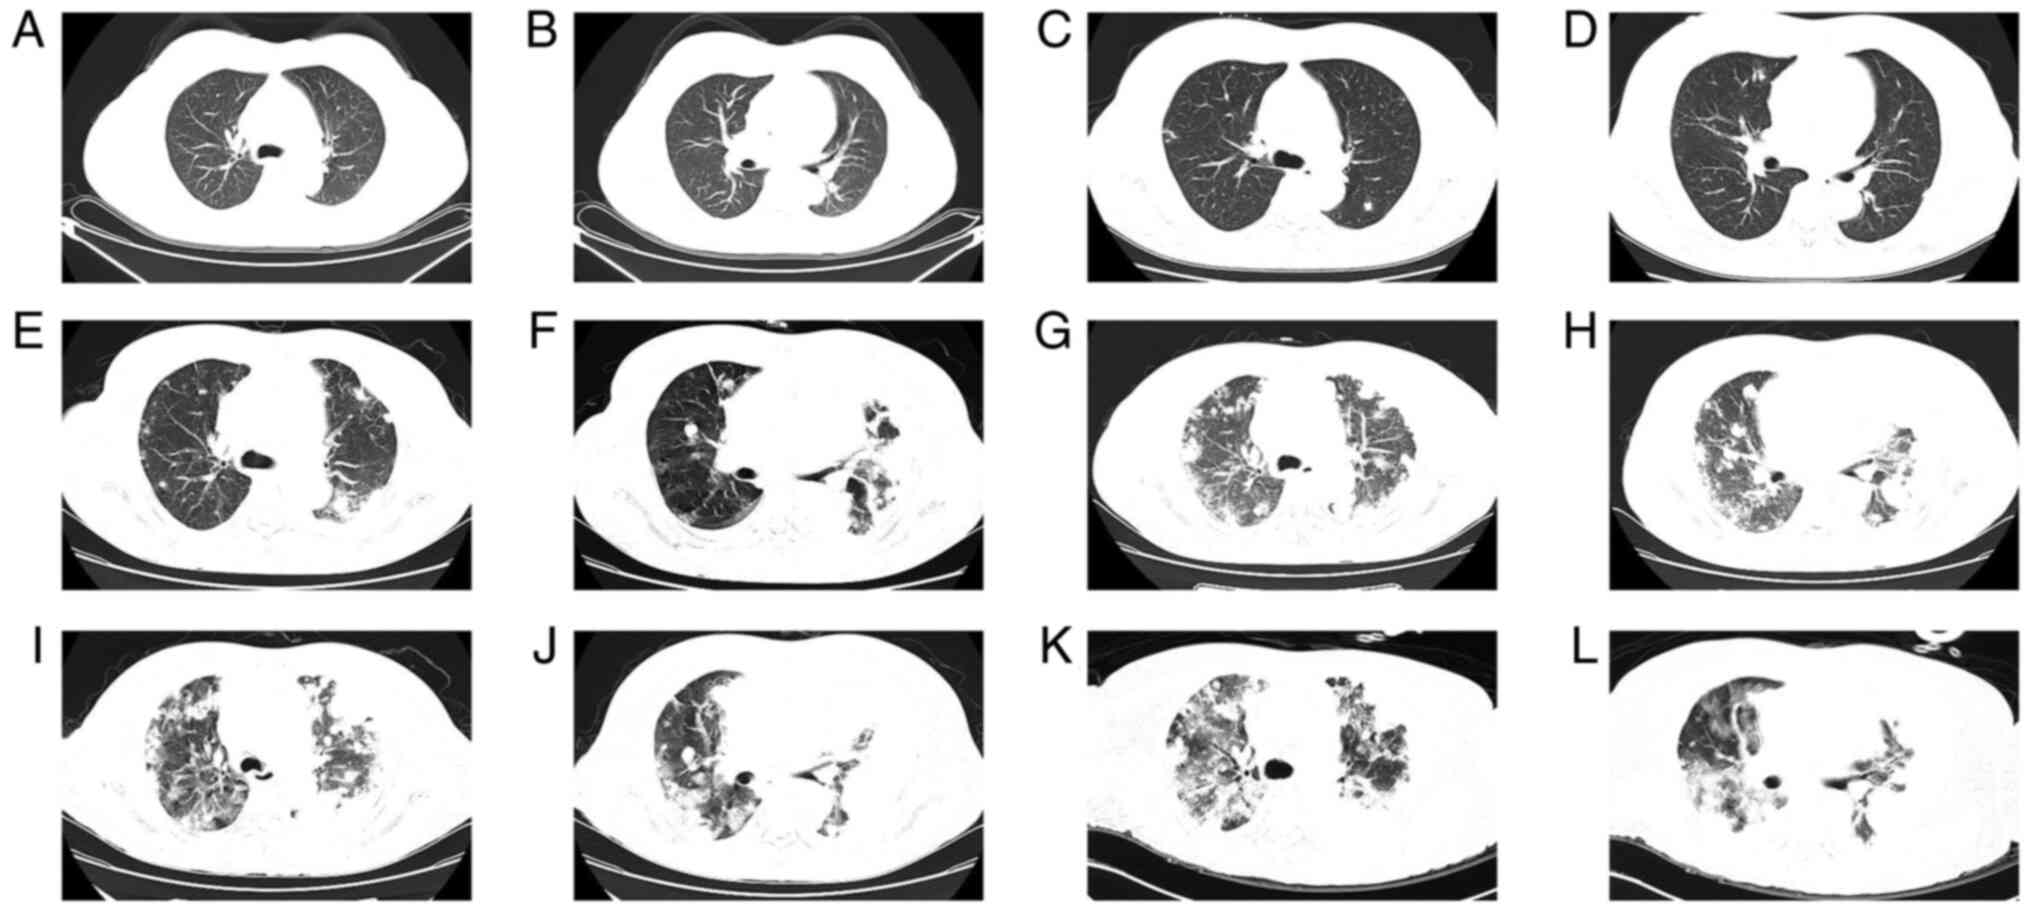

Primary pulmonary epithelioid angiosarcoma is a rare tumor type without any specific clinical and imaging features. Therefore, it is associated with high rates of misdiagnosis. The present study reports the case of a 54‑year‑old female patient who was admitted after complaining of cough, expectoration and bloody sputum for >5 months in May 2021. The patient reported a previous history of papillary thyroid carcinoma in 2003 and had undergone treatment through surgery, postoperative chemotherapy and iodine131 therapy. Chest computed tomography (CT) was performed in May 2021, which indicated that the disease had progressed rapidly since February 2021. CT‑guided lung biopsy and immunohistochemical staining of the tumor indicated positivity for CD31, CD34 and E26 transformation‑specific‑related gene markers. The tumor was negative for thyroid cancer‑associated antibodies; thus, a diagnosis of primary pulmonary epithelioid angiosarcoma was made. The patient died 3 months after the diagnosis. Primary pulmonary epithelioid angiosarcoma is a rare tumor type with high recurrence and metastasis rates. This tumor has no specific clinical symptoms and signs and is thus easily misdiagnosed. Biopsy is essential for diagnosis of the disease, particularly if patients have a tumor history.

Figure 1